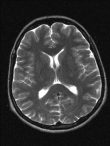

Un chist arahnoid este cel mai probabil sa se dezvolte in cap, dar se poate dezvolta si in jurul maduvei spinarii. Se numeste chist arahnoid, deoarece apare in spatiul dintre creier, coloana vertebrala si membrana arahnoida. Acesta este unul din cele trei straturi de membrana care inconjoara creierul si coloana vertebrala. Daca un chist arahnoid se dezvolta in cap, va creste intre creier si craniu sau in buzunarele din jurul creierului numite ventriculi.

Chisturile arahnoide sunt, de obicei, umplute cu lichid cefalorahidian (CSF). CSF este un lichid de protectie naturala care inconjoara creierul si coloana vertebrala. Peretii unui chist arahnoid nu permit acest fluid sa se scurga in sistemul CSF, determinand acumularea in interiorul acestuia.